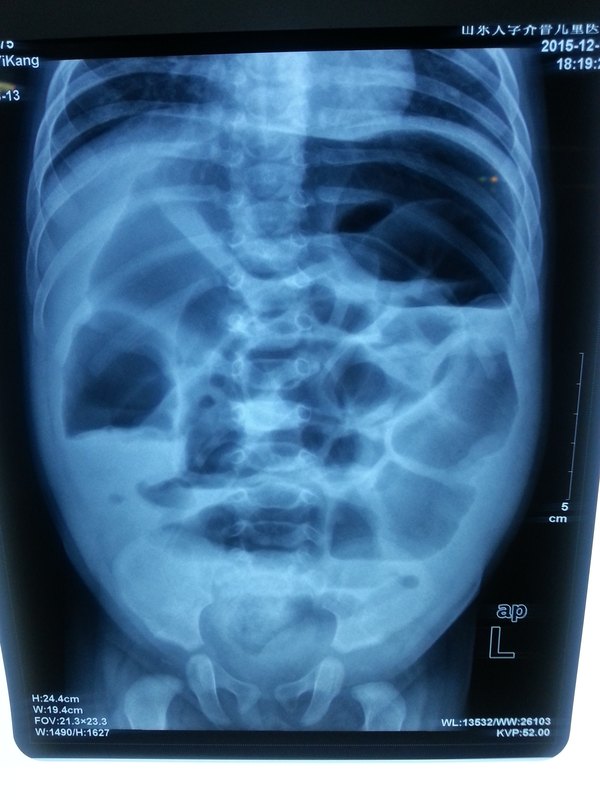

小兒吞食異物導(dǎo)致腸穿孔3歲男孩,腹痛,腹脹,發(fā)熱來(lái)診,并有嘔吐,黃綠色物。查體腹肌緊張,考慮腹膜炎,手術(shù)探查,術(shù)前彩超檢查提示腹腔異物,仍位于腸腔內(nèi),未穿透。術(shù)中見(jiàn)腹腔膿性滲液,腸管黏連,異物位于小腸內(nèi),再向近端探查發(fā)現(xiàn)腸壁穿孔(對(duì)沖)。取出異物,修補(bǔ)腸壁。